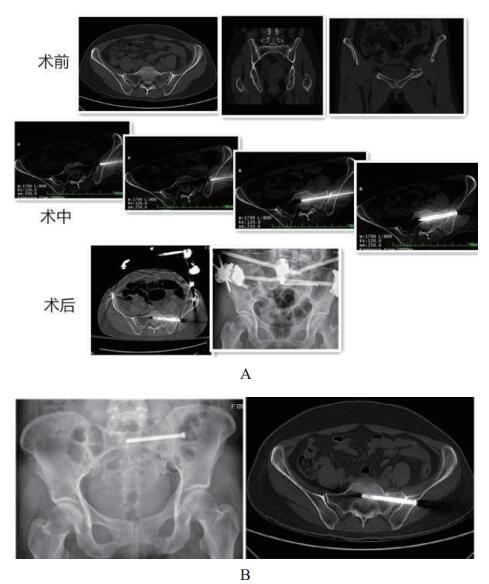

2.2 随访结果平均随访时间15.2个月(8~21个月)。所有的骨折均愈合,没有螺钉相关并发症,无血管神经并发症,切口愈合良好。12例患者使用了前环外固定支架(其中3例髂前下棘,9例髂嵴);4例前环重建钢板固定;3例髋臼骨折使用重建钢板固定。7.3 mm空心钉16根;6.5 mm空心钉3根;6根用了垫圈,空心钉长度平均为72 mm(55~85 mm)。由于是微创手术,所以出血量很少,难以准确计量。术后患者骨盆引起的疼痛均能得到明显缓解,末次随访的VAS评分平均为1.8。骨折复位情况通过Matta评分标准,优:14例,良:4例。功能评分采用Majeed评分标准,末次随访评分,优:11例,良:6例,可:1例,患者基本回到原来工作及生活。(典型病例见图 3,4)

| 图 3 患者,女,53岁,左侧骶骨骨折伴耻骨上下支骨折,术中置钉移动CT扫描4次,术后显示置钉位置好(A)。随访显示骨折愈合好(B)。 |

| 图 4 患者,女,53岁,左侧骶骨骨折伴耻骨上下支骨折,术中置钉移动CT扫描4次,术后显示置钉位置好(A)。随访显示骨折愈合好(B)。 |